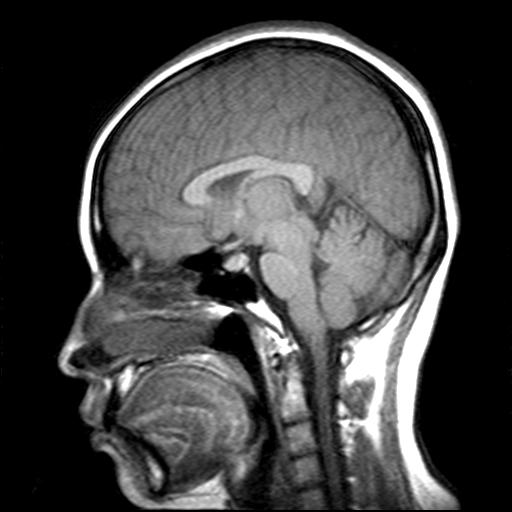

发热、头痛伴精神异常1周

较对称性脑白质异常信号,深部白质t2明显低信号(铁质沉积过多?)

考虑脑白质病变,请结合临床病史及实验室检查进一步分析。

f 23岁